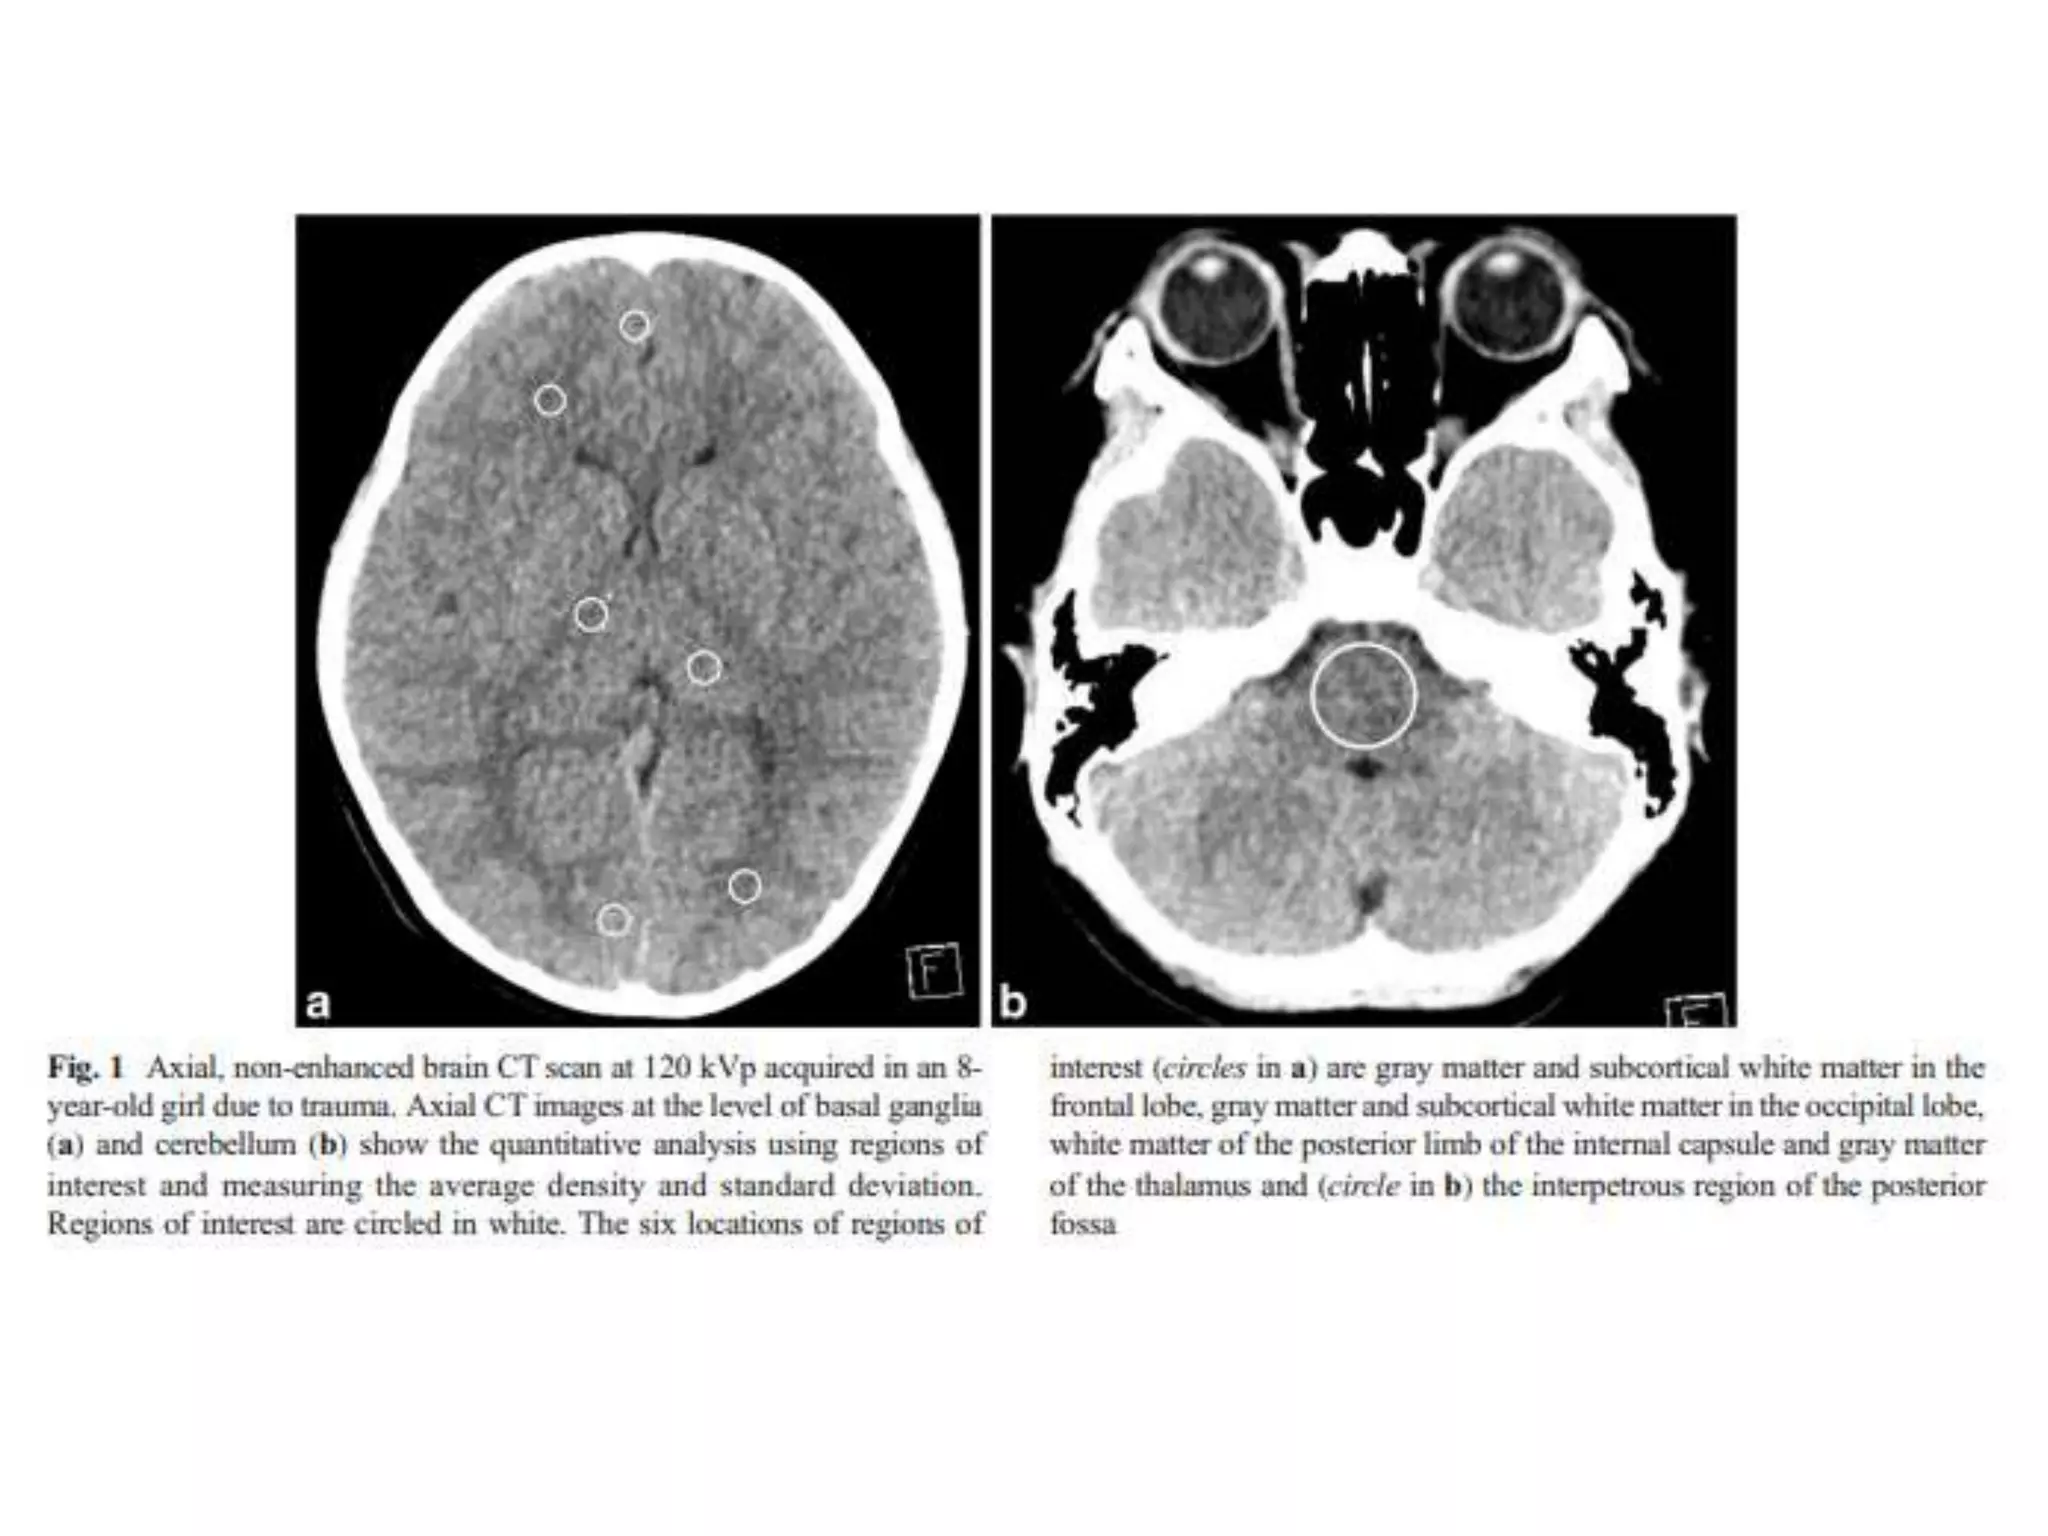

• 80 kV brain CT

– were shown to be with improved gray

matter-white matter contrast-to–noise ratios.

– Similar overall image quality

• 6.5% radiation dose reduction

• 80 kV brain CT can be an acceptable

technique to replace a standard 120 kV

CT scan in children

Conclusion • 80 kVbrain CT – were shown to be with improved gray matter-white matter contrast-to–noise ratios. – Similar overall image quality • 6.5% radiation dose reduction • 80 kV brain CT can be an acceptable technique to replace a standard 120 kV CT scan in children